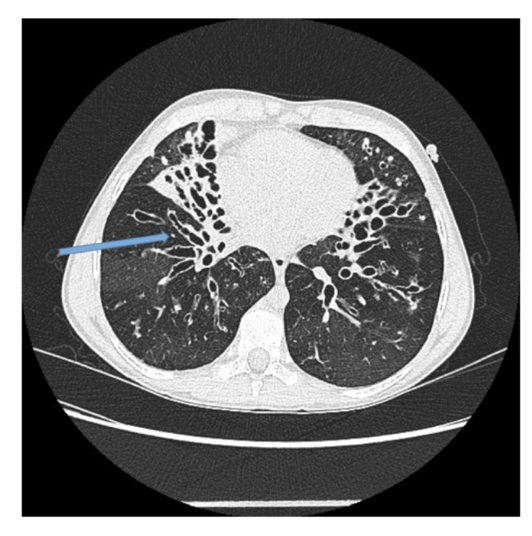

New cards

What is the CT + Pathology?

• HRCT

• Path = bronchiectasis: dilation of the bronchial wall due to chronic inflammation

• Ground glass appearance: hazy areas of increased attenuation through the lung.

• Bronchial wall thickening